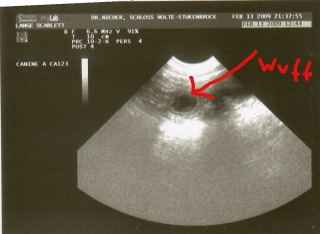

Das Foto vom Ultraschall (13.02.2009) ist da:

scully20090213001mitwuff.jpg

Na, jetzt ist schon die Hälfte der Tragezeit rum, Freitag ist der nächste Termin bei Dr. Nieder, dann gibt es neue Bilder, in größer ;-)

Scully ist fit und gesund, nur auf dem Sofa ist sie öfter als sonst zu finden.

15. Februar 2009

Letzten Freitag war Scully bei Dr. Nieder zum Ultraschall: Voila, sie ist trächtig. Die genaue Anzahl der Welpen ist zu diesem Zeitpunkt natürlich noch nicht erkennbar; das Foto zum Ultraschall liefern wir noch nach.